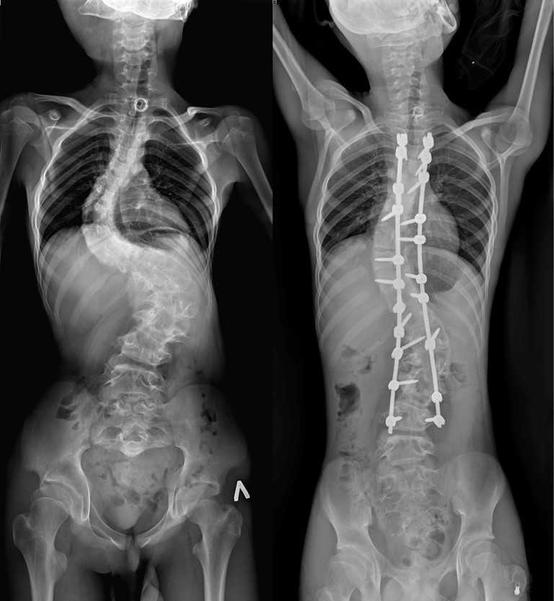

13-летний Мурат страдал от редчайшего генетического заболевания. Врачи провели ему операцию, которая длилась более семи часов. Как отмечают медики, кифотическая деформация грудного отдела позвоночника у юноши составляла более 110 градусов, а комбинированная сколиотическая — по 90 градусов в грудном и поясничном отделах.

В результате операции качество жизни Мурата значительно улучшится. Врачи говорят, что он сможет даже заниматься своим любимым делом — кататься на велосипеде. Болезнь обострилась у юноши около двух лет назад. Он поступил в больницу с существенным искривлением позвоночника.